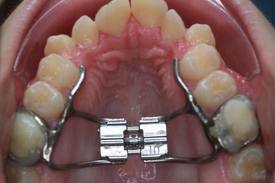

trans_GNE_modQuand la croissance est terminée, il est nécessaire d’associer un traitement à l’aide d’un disjoncteur avec un acte chirurgical.trans_ormco_rpe1 La chirurgie consiste à créer une fente dans l’os, puis l’appareil écartera tous les jours la fente afin qu’elle soit comblée par de l’os. Au niveau du maxillaire, l’appareil se situe au niveau du palais. Au niveau de la mandibule, en arrière des dents du bas.

La chirurgie est la même que l’ostéotomie maxillaire. Elle se déroule sous anesthésie générale. En plus de l’ostéotomie de Lefort 1, il sera réalisé une section du plateau palatin qui permet de “l’élargir” à l’aide de l’appareil mis en place par l’orthodontiste.

Au niveau de la mandibule, l’ostéotomie se situe au niveau du menton. Le principe est le même, elle consiste en la pose d’un disjoncteur à appuis dentaire les jours précédents l’intervention. La fente au niveau du menton permet d’augmenter la largeur de la mâchoire inférieure.